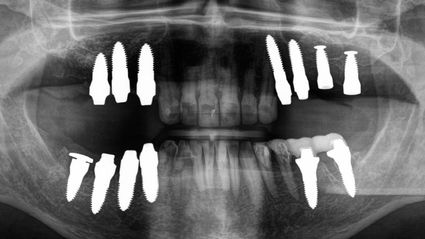

Vor